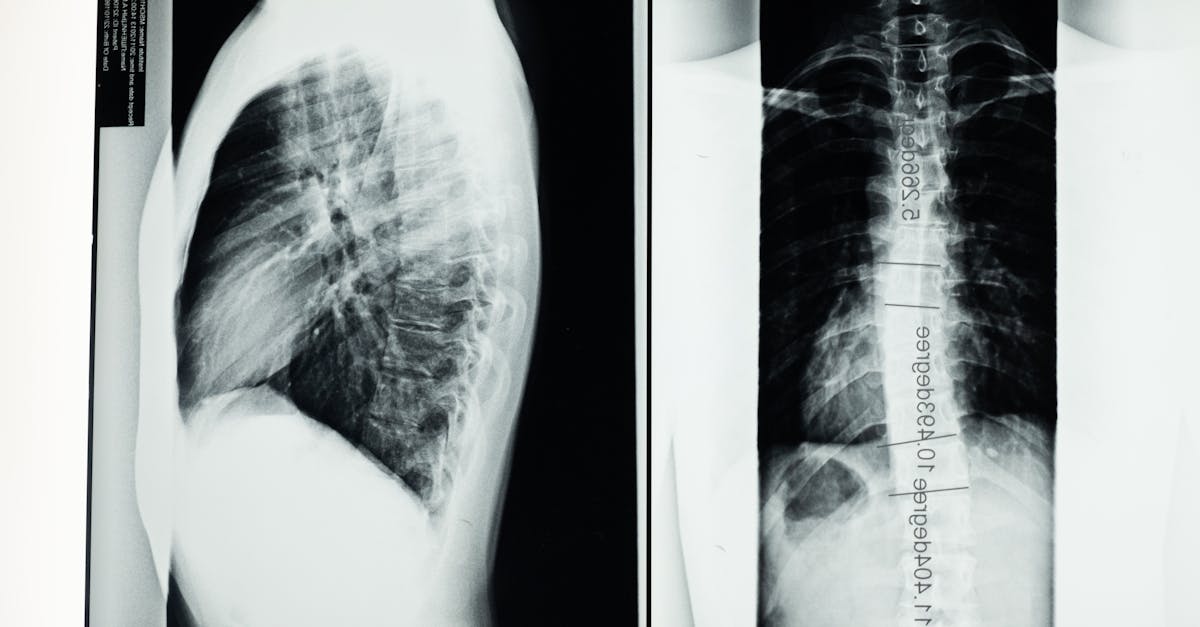

La décompression neurovertébrale est une technique thérapeutique qui utilise une traction douce pour créer un espace entre les vertèbres, réduisant ainsi la pression sur les disques intervertébraux. Cette méthode est particulièrement efficace pour traiter des conditions comme les hernies discales et la sténose spinale. Grâce à cette approche, les patients ressentent souvent un soulagement rapide et durable sans besoin d’interventions invasives.

La décompression neurovertébrale est une technique thérapeutique qui utilise une force de traction contrôlée pour créer un espace sans pression entre les vertèbres. Cela permet de réduire la pression exercée sur les disques intervertébraux et les nerfs voisins, favorisant ainsi la guérison des douleurs dorsales, cervicales et d’autres troubles associés à la colonne vertébrale. Cette méthode se distingue par son approche non invasive, évitant ainsi les risques liés aux interventions chirurgicales ou aux traitements médicamenteux prolongés.

La décompression neurovertébrale fonctionne sur le principe de la traction appliquée à la colonne vertébrale, créant un espace entre les vertèbres. Cela permet de réduire la pression sur les disques intervertébraux et les nerfs environnants, favorisant ainsi un processus de guérison naturel. Ce soulagement des tensions au niveau de la colonne vertébrale est particulièrement bénéfique pour les personnes souffrant d’hernie discale ou de sténose spinale. En évitant d’avoir recours à des médicaments, les patients peuvent à la fois bénéficier d’un soulagement immédiat tout en préservant leur santé à long terme.

Un des principaux avantages de la décompression neurovertébrale réside dans sa capacité à traiter une variété de troubles de la colonne vertébrale, tels que les hernies discales ou les douleurs lombaires. Grâce à des techniques de traction ciblées, cette approche thérapeutique permet de créer un espace négatif au sein de la colonne, facilitant ainsi la circulation des fluides et la réduction de l’inflammation. Cela peut entraîner un soulagement durable sans nécessiter la prise de médicaments puissants.